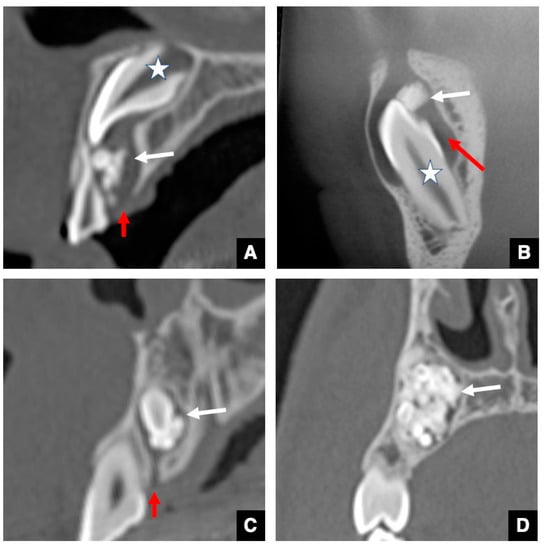

2.3. CT Images of GT in Maxillary Anterior Teeth with Delayed Eruption and Mesiodens